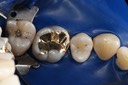

Wayne Chin #14 caries removal